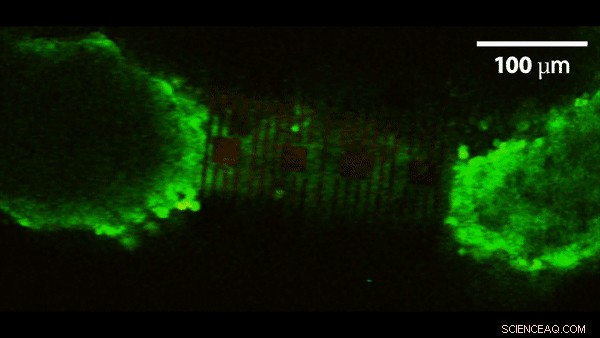

A 3D self-rolled biosensor array gripping a 3D cardiac spheroid. Credit: Carnegie Mellon University

Researchers from Carnegie Mellon University (CMU) and Nanyang Technological University, Singapore (NTU Singapore) have developed an organ-on-an-electronic-chip platform, which uses bioelectrical sensors to measure the electrophysiology of the heart cells in three dimensions. These 3-D, self-rolling biosensor arrays coil up over heart cell spheroid tissues to form an "organ-on-e-chip," thus enabling the researchers to study how cells communicate with each other in multicellular systems such as the heart.

The researchers tested the platform on cardiac spheroids, or elongated organoids made of heart cells. These 3-D heart spheroids are about the width of 2-3 human hairs. Coiling the platform over the spheroid allows the researchers to collect electrical signal readings with high precision.

Calcium ion activity imaging of an encapsulated cardiac spheroid in the biosensor array. Credit: Carnegie Mellon University College of Engineering